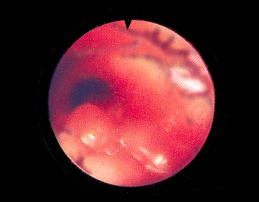

La broncoscopia preoperatoria es un procedimiento obligatorio muy delicado en la estenosis traqueal, permite evaluar el lugar, severidad y longitud de la estenosis, adicionalmente el estado de la via aerea.

• 8 semanas mas tarde a su egreso del hospital, es admitido por síntomas y signos agudos alarmantes de insuficiencia ventilatoria y asfixia, que amerita traqueotomía para el manejo de la vía aérea, por supuesta estenosis traqueal cervical según sus antecedentes, la posterior evaluación endoscópica de la vía aérea, demostró proceso estenótico severo de  traquea torácica a 3 o 4 cm. supracarinal y traqueobronquitis severa, requirió intubación con tubo traqueal No 5, distal a la estenosis desde la traqueotomía. Tratado con antibióticos, anti inflamatorios y esteroides no se logró corregir los problemas, nueva endoscopia de vía aérea confirmó los hallazgos anteriores de conducto traqueal estenosado a 6 mm. de diámetro aproximadamente, en una extensión de 2 cm. y situado a 3.5 cm por encima de la carina principal, el resto de la vía aérea y la traqueotomía cervical en el 6to. anillo traqueal anterior se apreciaron bién, debido a los numerosos episodios de obstrucción de vía aérea que requirió cambios consecutivos del tubo de traqueotomía por la persistencia de la estenosis descrita, se decide su intervención y corrección quirúrgica.